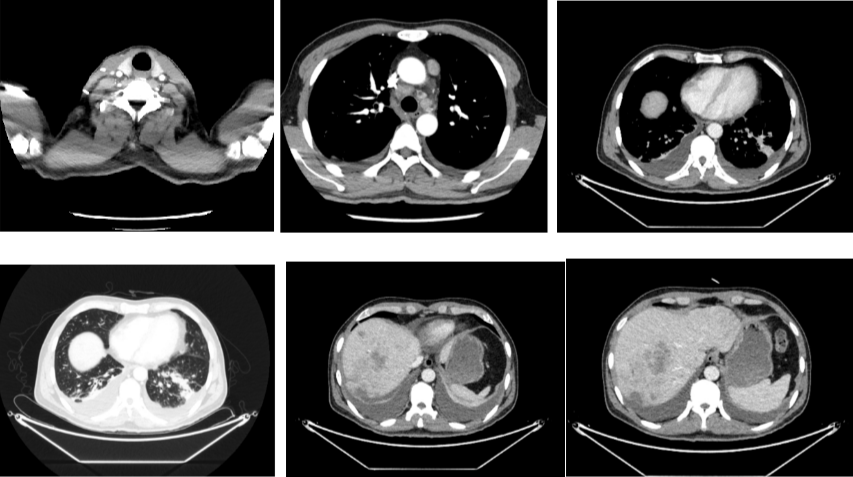

外院CT检查提示:1、两肺多发斑片状、结节影,性质待定,转移瘤?2、纵隔内多发肿大淋巴结;3、肝实质多发稍低密度影,性质待定(转移瘤可能性大)

2018-03-08 PET/CT示:胃癌(?)并全身多发淋巴结转移、肝脏多发转移、双肺上叶多发转移;

2018-11-14 CT(8周期化疗后):PD?

胃癌并肝转移化疗后,肝内转移灶大致同期;

慢性肝病,脾大、门脉高压(食管下段-胃底静脉曲张);

双肾小囊肿;

右肺中叶外侧段、左肺上叶下舌段及右肺下叶后基底段慢性炎症;

右肺上叶前段实性微小结节,炎性结节?建议定期复查;

纵隔淋巴结转移瘤,复查大致同前。